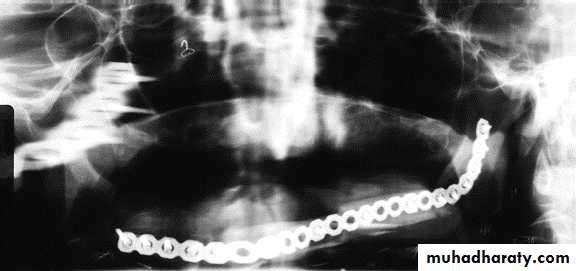

• Maintaining or re-establishing mand. Continuity, by fixation plates.• Sectioning in ramus area.

Fixation indication:

Resection confined to mand.+ little soft tissue loss

Min. scar contracture+ enough soft tisssue for closure.Ms. Imbalance + compromised proprioception

contraindication:

Composite resection ; radical neck dessection ; radiotherapy ;1ry closure.Profound scar contracture ;worsened man. deviation